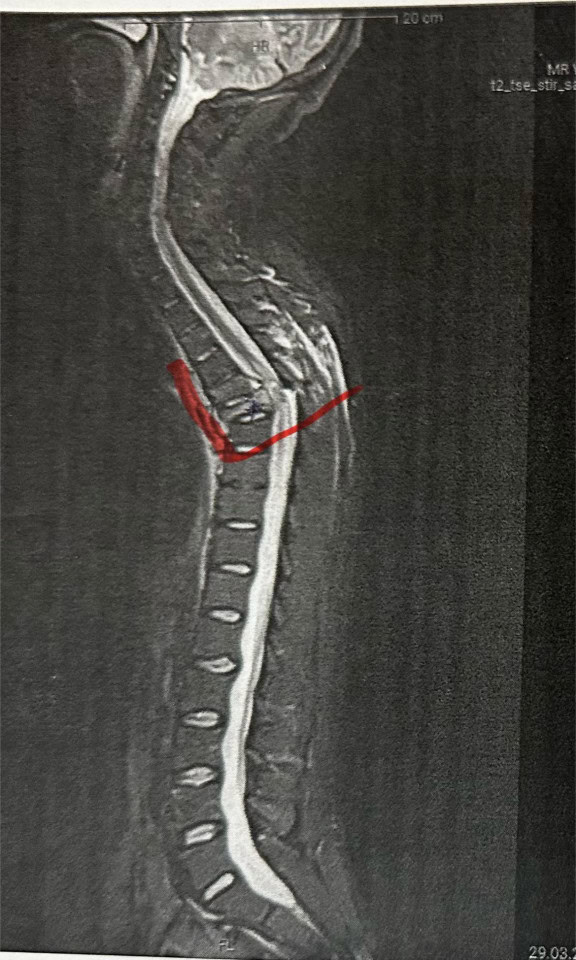

Noch am selben Tag wurde Kevin Wilkniß in die Uniklinik Leipzig gebracht und operiert. Der siebte Brustwirbel war gebrochen, mehrere Rippen ebenfalls. Zudem war die Lunge verletzt, was eine weitere Operation verzögerte. „Die erste OP war nur das Nötigste, sie mussten abbrechen, weil mein Kreislauf kollabiert ist.“ Erst später, in einer Spezialklinik für Querschnittslähmung, konnte der beschädigte Wirbel ersetzt und der Rücken stabilisiert werden – durch mehrere riskante Eingriffe.